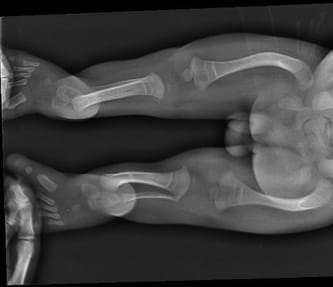

Adaś urodził się siódmego października i mimo czarnych wizji lekarzy przeżył więcej niż kilka krótkich chwil na tej ziemi. Pomimo, iż lekarze zaszufladkowali go i przykleili mu „łatkę” wrodzonej łamliwość my uparcie udowadnialiśmy im, że się mylą. I choć kazali go nie przytulać, nosić na drewnianej deseczce i najlepiej w ogóle nie rehabilitować my sami działając po omacku i kierując się własną intuicją pokonywaliśmy strach przed chorobą i z dnia na dzień, z tygodnia na tydzień byliśmy coraz odważniejsi w jego pielęgnacji uświadamiając sobie, że Adaś nie jest krucha istotką, ale silnym i walecznym młodym człowiekiem, na którego wydano niesprawiedliwy wyrok. Nasze przekonanie potwierdziły badania genetyczne, które wykluczyły wrodzoną łamliwość kości. Z czasem szukając najlepszych specjalistów z zakresu ortopedii trafiliśmy na doktora Paley, który potrafił w prawidłowy sposób zdiagnozować problem Adasia. Jego nóżki nie były nigdy złamane a jedynie wykrzywione. Obraz USG w ciąży, jak również badania RTG sprawiały mylne wrażenie kości po złamaniu.

U Adasia zdiagnozowano rzadką wadę genetyczną, która fachowo nazywa się dysplazją kampomeliczną. Na świecie żyje niezwykle mało osób z tą chorobą z dwóch powodów: po pierwsze, jeśli zostanie wykryta w trakcie ciąży, to zwykle rodzicom sugerowana jest aborcja, której byliśmy na prawdę blisko, po drugie jeśli takie dziecko przychodzi na świat to zwykle umiera z powodu niewydolności oddechowej. Przeżywa 7% i najczęściej żyją z rurką tracheostomijną. Mutacja, którą ma Adaś jest jeszcze bardziej nietypowa, bo póki co nie odnotowano jej w żadnym badaniu genetycznym. Ma to jednak swoje plusy, bo Adaś żyje bez takiej rurki i do tej pory nie ma problemów z oddychaniem. Jego choroba objawia się jednak licznymi problemami ortopedycznymi, przede wszystkim w obrębie kręgosłupa i nóg. Adaś wymaga ciągłej rehabilitacji i wielu specjalistycznych konsultacji lekarskich. Poddano w wątpliwość możliwość samodzielnego poruszania się Adasia. Odwiedziliśmy całą rzeszę ortopedów w Polsce i za granicą.

Adaś po raz kolejny udowodnił jakim jest wojownikiem, zaczął samodzielnie chodzić. Jednak jego nóżki są w wielu miejscach bardzo powykrzywiane. Adaś potrzebuje serii operacji, które umożliwią mu prawidłowe chodzenie, uniknięcie zwichnięcia stawów biodrowych oraz poprawią komfort życia. Jego wada jest ekstremalnie rzadka a seria rekonstrukcji, których potrzebuje jest bardzo rozległa (m.in. prostowanie kości udowych, kości podudzia, rekonstrukcja stóp, korekcja bioder i wiele innych zabiegów na tzw. tkankach miękkich). Po wielu poszukiwaniach los po raz kolejny postawił na naszej drodze doktora Paleya, który ma swoją klinikę na Florydzie. Doktor podjął się leczenia Adasia, co więcej, zminimalizowania ilości operacji i tym samym zmniejszenia dziecku ilości bólu i cierpienia. Co więcej, w naszym przypadku zgodził się na wykonanie operacji w Polsce. Jest to dla nas niezwykła szansa aby zapewnić synowi prawidłowy rozwój i w miarę normalne funkcjonowanie wśród rówieśników.